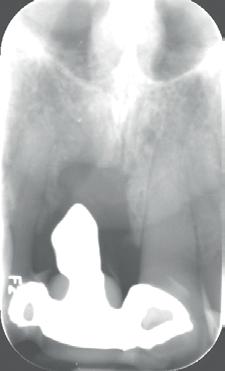

4: Horizontale doorsnede CBCT met radiolucentie mesiopalatinaal van de 11

Er wordt een CBCT gemaakt die een laesie aan de mesiopalatinale zijde van 11 laat zien (afbeelding 4).

Aangezien dit zou kunnen duiden op een crack of fractuur, wordt besloten om het element te openen en te inspecteren.